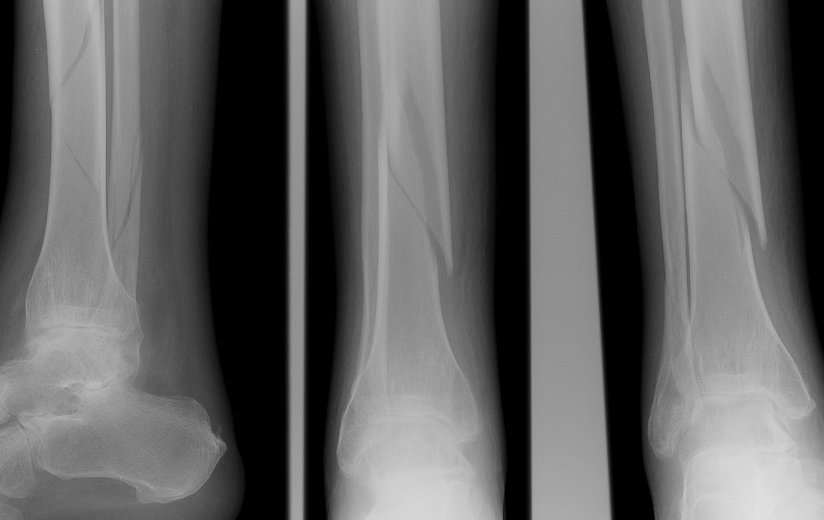

Return to Tibia and Fibula Fractures